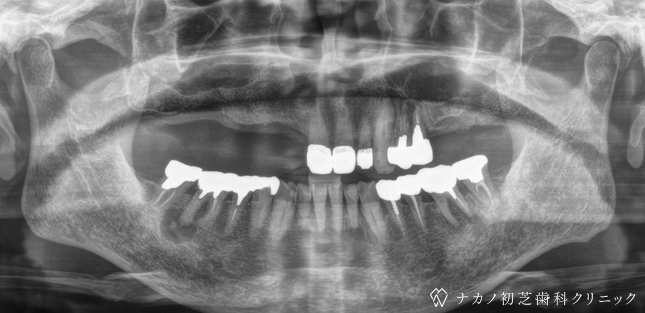

インプラント・13本 (60代女性)

BEFORE

AFTER

年齢 60代女性

治療内容 インプラント治療13本(骨造成の併用)

インプラント治療とは、歯を抜いた所にチタン製の人工歯根を埋入し、その上に歯を入れる方法です。骨を増やすことで、より審美的に治療が出来ました。費用 1本 400,000円(税込 440,000円)

リスク・副作用

腫れ・疼痛・違和感を感じるなどの症状を生じることがあります。